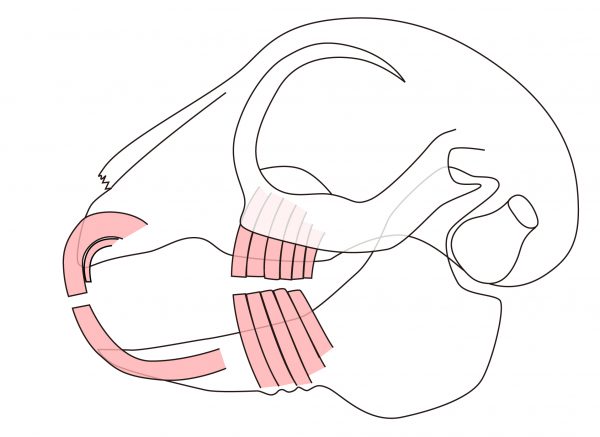

ウサギの臼歯は正面から見ると下のイラストのようにほぼ垂直に生えており、上顎の左右の臼歯は下顎の臼歯よりも幅広く位置しているのが特徴です。

咬耗が減少することで、臼歯は伸びるだけでなく、縁が尖る傾向にあります。

上顎の臼歯は頬側に、下顎の臼歯は舌側に向かって、臼歯の一部が棘のように尖って伸びます。

この棘をスパイク(Spike)と呼ばれ、舌や粘膜に裂傷を与え、口痛および流涎の原因になります。